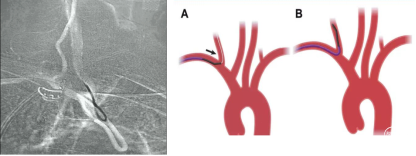

关键技术:无交换 导引导管到位技术 (外管+猪尾造影导管)

经绕动脉完成右侧颈内动脉介入通路建立示意图

关键技术:

无交换 导引导管到位技术 (外管+西蒙导管)

1、经绕动脉完成的左侧颈内动脉介入通路建立示意图